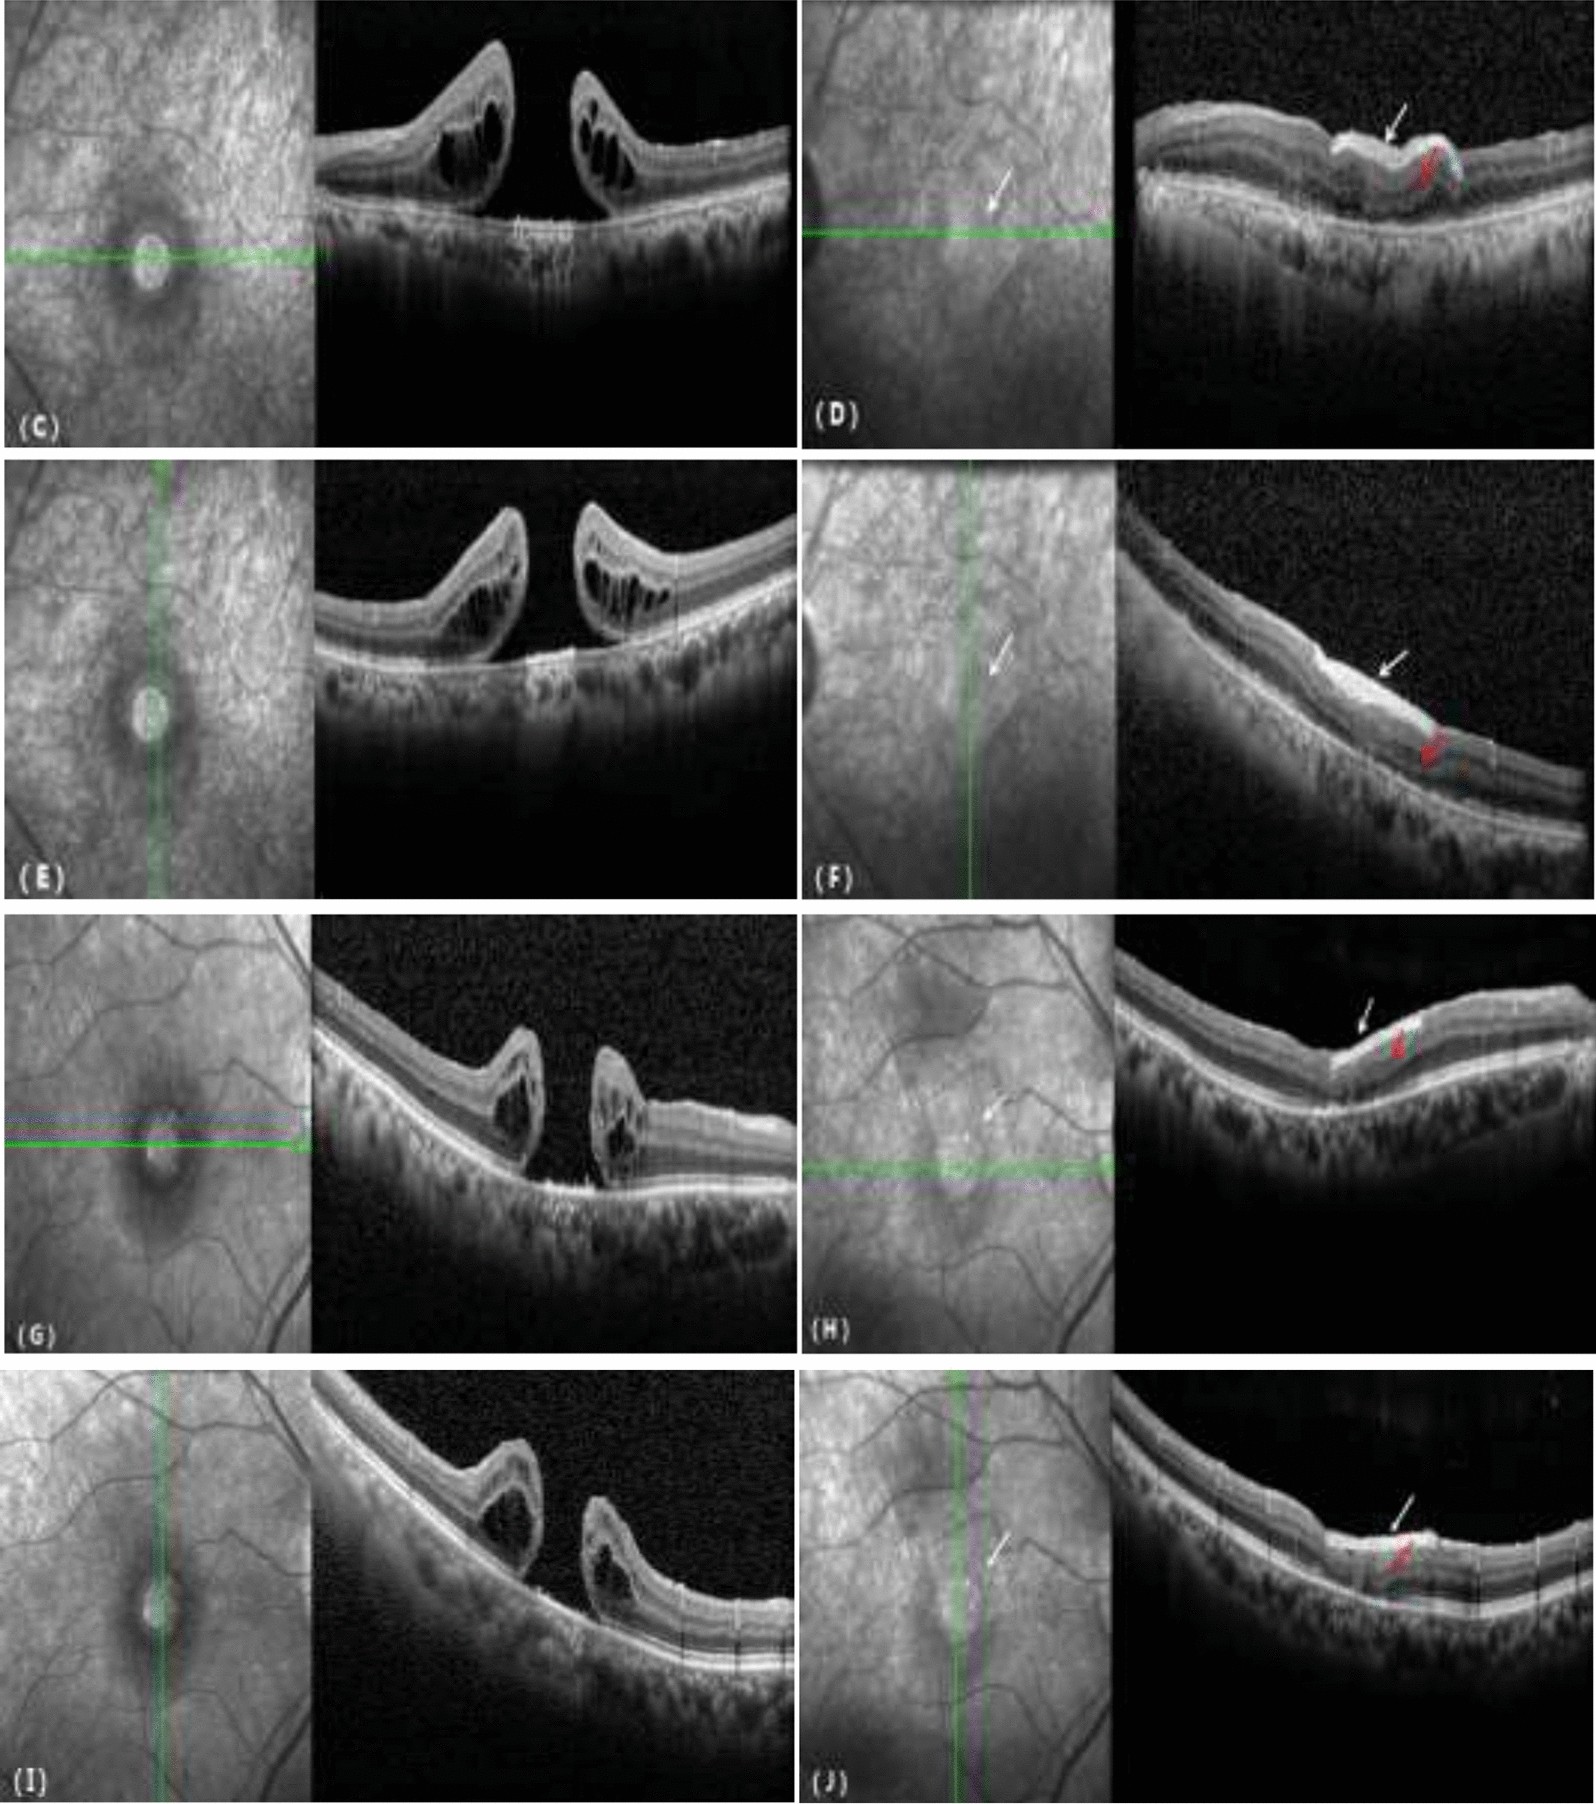

Figure 2

From: The use of biological amniotic membranes in the treatment of recurrent macular holes

Comparison of OCT before and after treatment for a recurrent macular hole. (C, E, G, I) MH before surgery. (D, F, H, J) The MH was covered by the bAM (white arrow), the MH was closed, the outer structure of the retina was progressively repaired, and the ellipsoid zone was continuous (red arrow).